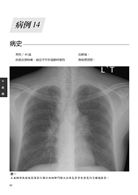

病例14 類肉瘤(Sarcoidosis) 62